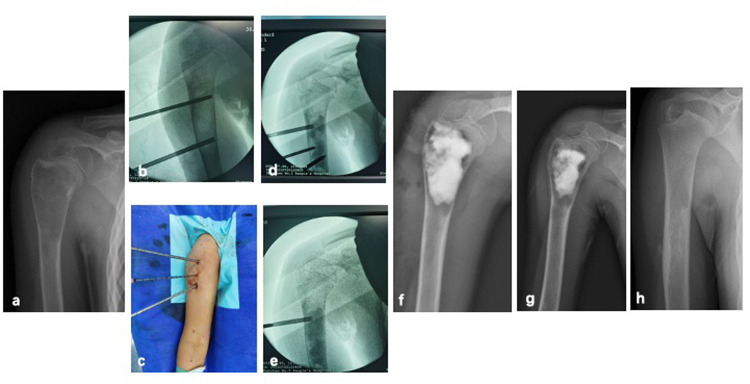

Methods: All patients underwent the PAIB procedure. Postoperative evaluation involved radiographic assessment to monitor recurrence and identify potential complications, with magnetic resonance imaging (MRI) performed when clinically indicated.

Results: In this cohort of 36 patients with SBC treated using the PAIB technique, the mean follow-up duration was 33.5 months (range: 12-66 months). Recurrence occurred in 6 patients (16.6%), including one case complicated by a pathological fracture. Five of the recurrent cases underwent repeat PAIB procedures, resulting in complete resolution in two patients. Postoperative imaging revealed small residual cysts in three cases. Bone healing was successfully achieved in 32 patients. Graft bone exudation, identified as a potential risk factor for recurrence, was observed in seven patients. All patients exhibited satisfactory functional outcomes throughout the follow-up period.

Abstract Image